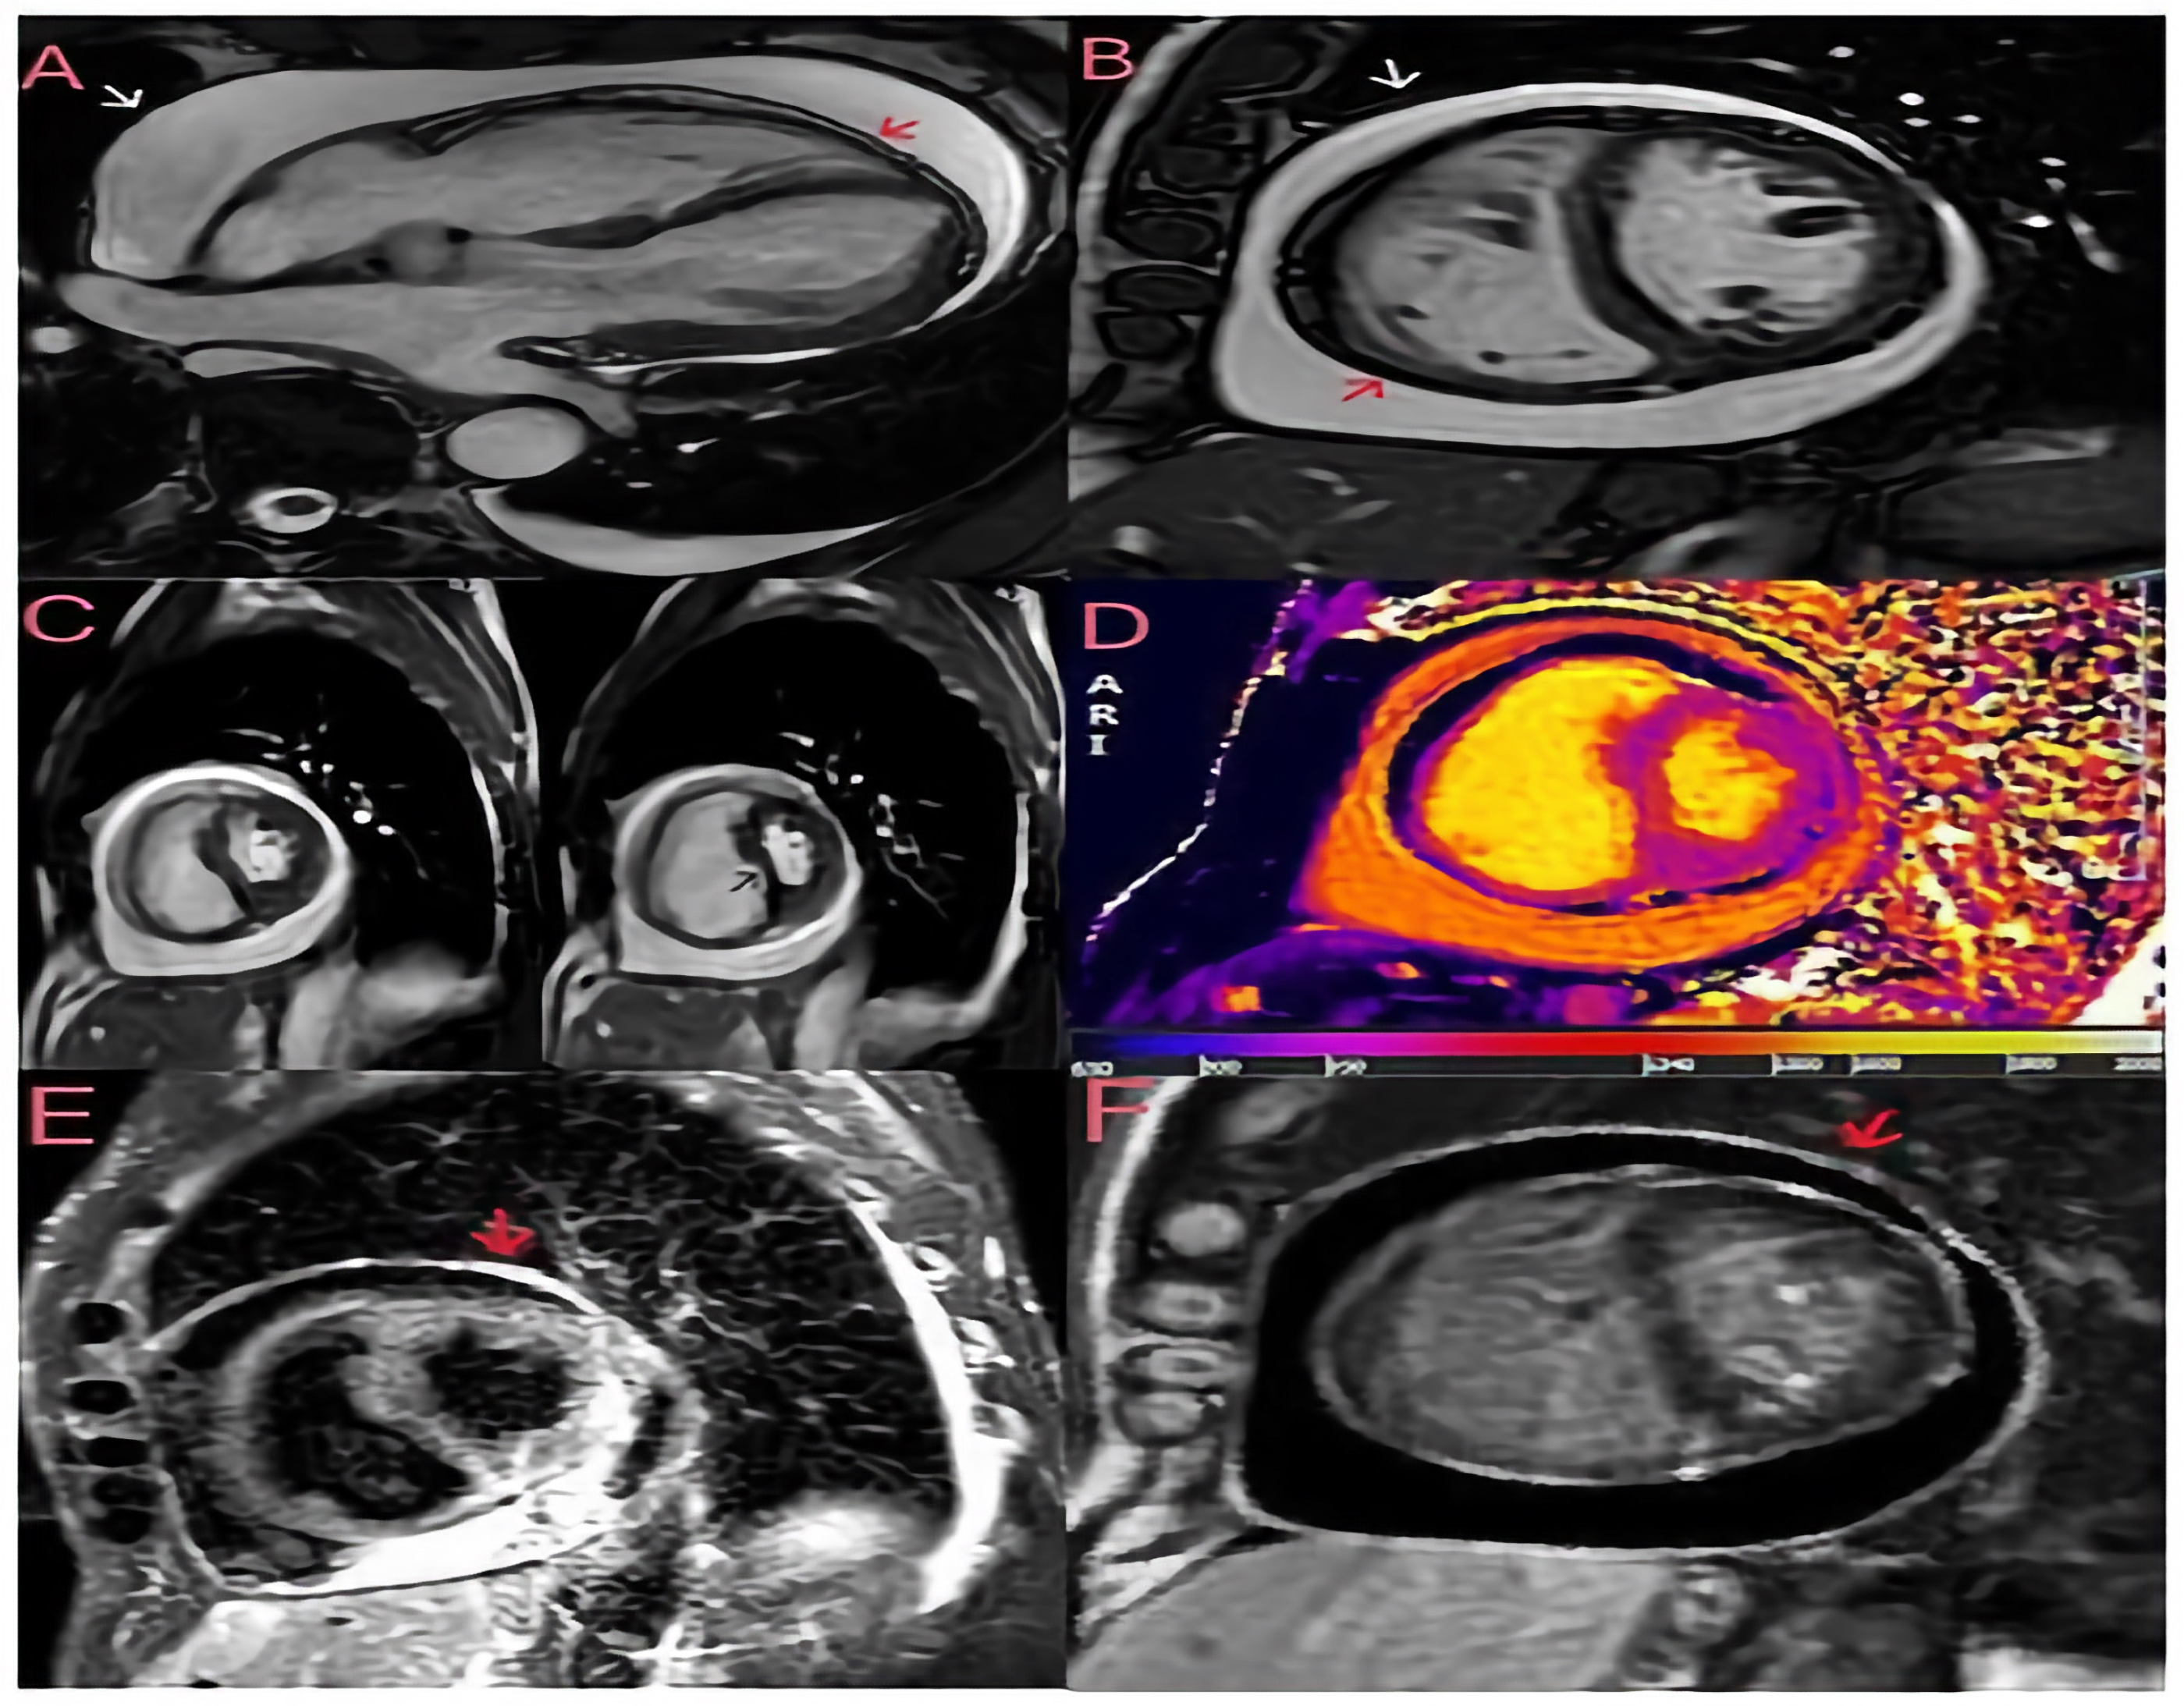

Figure 2. Cardiac magnetic resonance imaging (CMRI) was performed to assess the patient’s pericardial disease prior to referral to cardiac surgery. Breath-hold steady-state free precession (SSFP) cine of bright blood horizontal long axis (A) and midventricular short axis (B) views with evidence of a large pericardial effusion without compression of the ventricles in late diastole. The visceral (red arrow) and parietal (white arrow) pericardial layers are slightly thickened (3 mm). (C) Free-breathing SSFP cine in real time showing ventricular interdependence as a sign of constrictive pathophysiology; the left panel was taken during expiration, and the right panel during inspiration, showing septal bounce (black arrow) and crushing of the left ventricular chamber during inspiration. (D) The native T1 mapping sequence (modified look-locker inversion recovery) shows increased T1 times in the pericardium. (E) A short tau inversion recovery (STIR) T2 sequence showing pericardial hyperintensity (red arrow) compatible with oedema. (F) A late gadolinium enhancement (LGE) phase-sensitive inversion recovery (PSIR) sequence showing increased signal intensity in the pericardial layers (red arrow). The finding of a large pericardial effusion without tamponade and the widespread inflammation on the tissue characterisation images suggest subacute pericarditis with transient constrictive physiology, which accounts for 9–17% of cases of constrictive pericarditis and may resolve spontaneously within a few months [2,3]. Consequently, the patient was started on anti-inflammatory treatment with 600 mg of ibuprofen three times daily and 1 g of colchicine daily, resulting in clinical improvement, normalisation of inflammatory markers and discharge to home. During the follow-up, ibuprofen was progressively tapered to discontinuation, and at the last follow-up visit in October 2024, the patient was asymptomatic with no signs of volume overload and a normal plasma protein C level. This clinical case highlights the importance of assessing the chronicity of the disease by imaging in patients with constrictive pericarditis to differentiate between chronic and transient constriction, as acute/subacute cases may respond to medical therapy. Even though TTE is the imaging modality of choice for haemodynamic assessment, tissue characterisation with CMR is essential to diagnose the different phases of the pericardial inflammatory process, helping to differentiate an acute/subacute process (STIR+ and LGE+) from a chronic one (LGE+ and STIR-). Also of fundamental importance is the ability of cardiac magnetic resonance imaging to better assess the extent of pericardial effusion and pericardial thickening (a thickness > 3 mm tends to indicate chronic constrictive pericarditis). Such differentiation is crucial for tailored therapy; indeed, pericardiectomy is required in appropriate patients with chronic constrictive pericarditis [4]. In contrast, anti-inflammatory therapy is preferred in patients with transient constrictive pericarditis [5].

Diagnostics 14 02642 g002